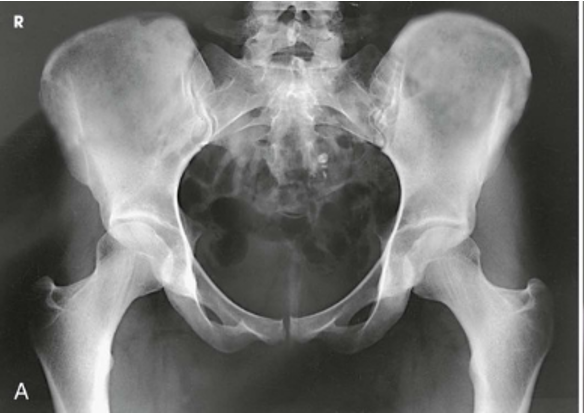

AP Projection; Pelvis and Proximal Femora (CR & SS)

The image shows an AP projection of the pelvis and of the head, neck, trochanters, and proximal one third or one fourth of the shaft of the femora

AP Projection; Pelvis and Proximal Femora